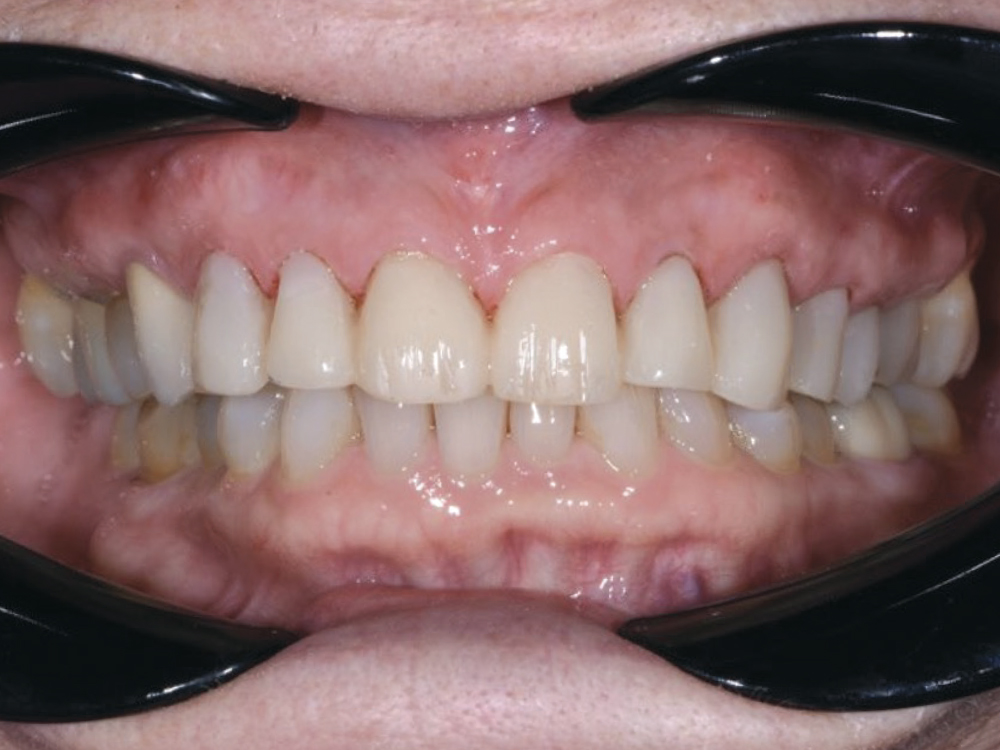

he gingivectomy on #8 & #9 resulted in gingival symmetry

The restorations were seated with Variolink® Esthetic resin cement (Ivoclar Vivadent)

Figures 8a, 8b: The gingivectomy on #8 & #9 resulted in gingival symmetry. The restorations were seated with Variolink® Esthetic resin cement (Ivoclar Vivadent). After tack-curing to facilitate cleanup, I removed excess cement and completed light curing from all aspects to ensure full polymerization. This sequence produced a durable and predictable bond while preserving the customized esthetic characterization of the Obsidian restorations.